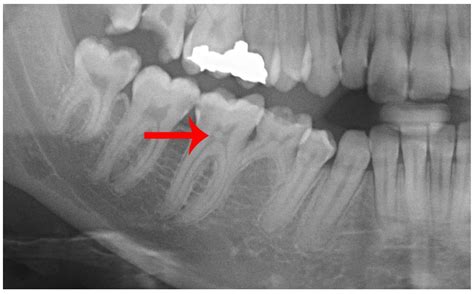

• X-Rays: Dental X-rays to detect cavities, fractures, or other abnormalities within the tooth.